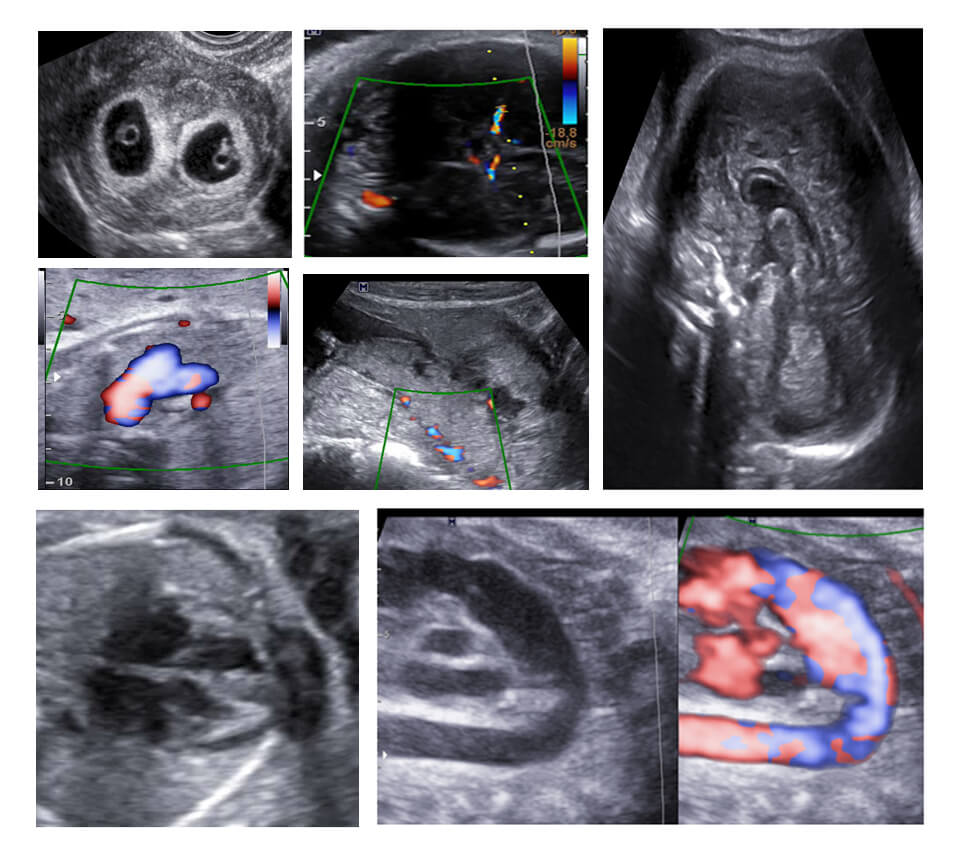

MODULE 7 :- CARDIAC AND MISCELLANEOUS

FETAL CARDIAC SCANNING : 4CH / OUTFLOW/ 3VV/ 3VT/ SAG/ OBLVIEWS, MAJOR CARDIAC ABNORMALITIES/ TWINS/ FETAL ANEMIA/ PLACENTA ACCRETA/ NEUROSONOGRAPHY AT A GLANCE